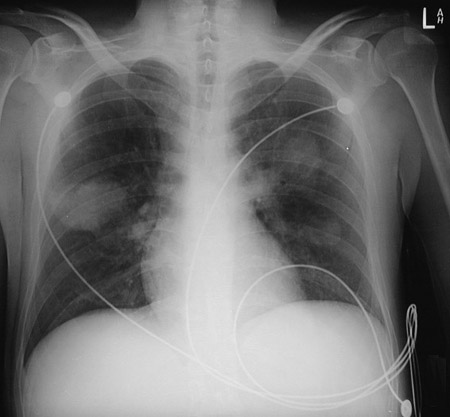

| This PA chest radiograph demonstrates extensive bilateral infiltrates made even more dense through hemorrhage from vascular damage by infection with Pseudomonas aeruginosa. The film below was taken only two hours after the one above, indicating how virulent this process can be. |